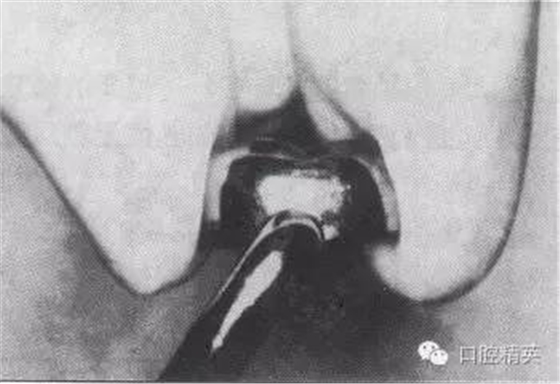

3)修整預成冠:參照所制備牙的牙冠高度及頸緣曲線形態(tài),剪除、修整預成冠的高度及頸緣,頸緣以達齦下0.5-1.0mm為妥。用各種冠鉗調(diào)整頜面的凹凸、恢復牙冠應有的隆起、縮緊牙頸部,盡力形成合適的解剖形態(tài)。

4)磨光頸緣、試戴合適:用金屬剪修剪過的頸緣必須以細砂輪、橡皮輪等磨光,以免刺傷牙齦。粘固前必須調(diào)試,仔細檢查頜面有無過高、牙頸部是否密合、成品冠的軸對修復牙及其在牙列中是否協(xié)調(diào)并觀察其與鄰牙的關系等。

a.制備牙體

b.選擇預成冠

c.修剪冠緣

d.修整冠外形

e.磨光